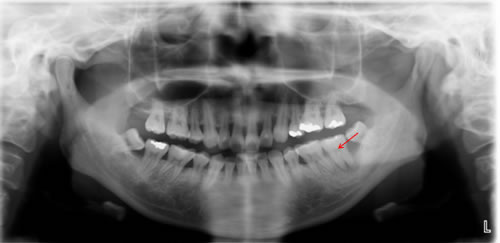

■37歳 女性 左下奥歯が腫れて痛い

![]() |

|

治療前のレントゲン |